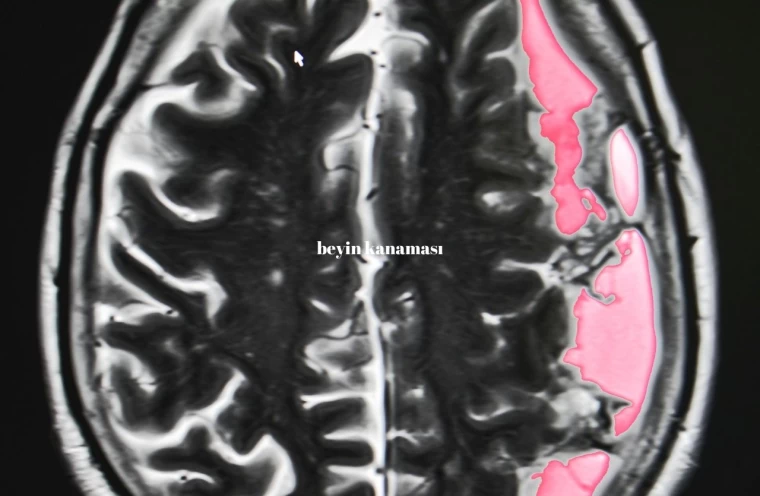

Beyin kanaması, aniden gelişen ciddi bir tıbbi durumdur ve beynin içerisindeki kan damarlarının patlaması sonucu meydana gelir. Bu durum, beynin normal fonksiyonlarını bozan bir basınca yol açar. Genellikle bir travma veya yüksek tansiyon gibi sebeplerden kaynaklanan beyin kanaması, anında müdahale gerektiren ve ölümcül sonuçlar doğurabilecek bir durumdur. Beyin kanamasının belirtilerini ve nasıl anlaşılabileceğini anlamak, erken müdahale şansını artırır. Bu yazıda, beyin kanaması belirtileri ve bu durumun risk faktörleri hakkında detaylı bilgi vereceğiz.

Beyin kanaması, hemen her zaman tehlikelidir, ancak bazı durumlarda daha büyük riskler taşır. Özellikle kanamanın büyük olduğu ve beyin dokusuna ciddi baskı yaptığı durumlar son derece tehlikelidir. Kanamanın gerçekleştiği bölge de önemlidir. Beynin hayati fonksiyonları kontrol eden bölgelerinde meydana gelen kanamalar, solunum durması, kalp atışı düzensizliği ve bilinç kaybı gibi ölümcül sonuçlara yol açabilir. Eğer beyin kanaması erken fark edilmez ve tıbbi müdahale gecikirse, kalıcı beyin hasarları veya ölüm riski artar.

Beyin kanamasının ilk belirtileri, kanamanın yerine ve şiddetine bağlı olarak değişir. Ancak genel olarak, ani ve şiddetli baş ağrısı en yaygın belirtidir. Bunun yanında bulantı, kusma, görme bozuklukları, konuşma zorluğu, denge kaybı, yüz veya vücutta ani uyuşma ve bilinç bulanıklığı da görülebilir. Bu belirtiler, özellikle ani ve beklenmedik bir şekilde ortaya çıkıyorsa, derhal acil tıbbi yardım alınmalıdır. Zamanında müdahale, beyin kanamasının yol açabileceği kalıcı hasarların önlenmesinde kritik rol oynar.